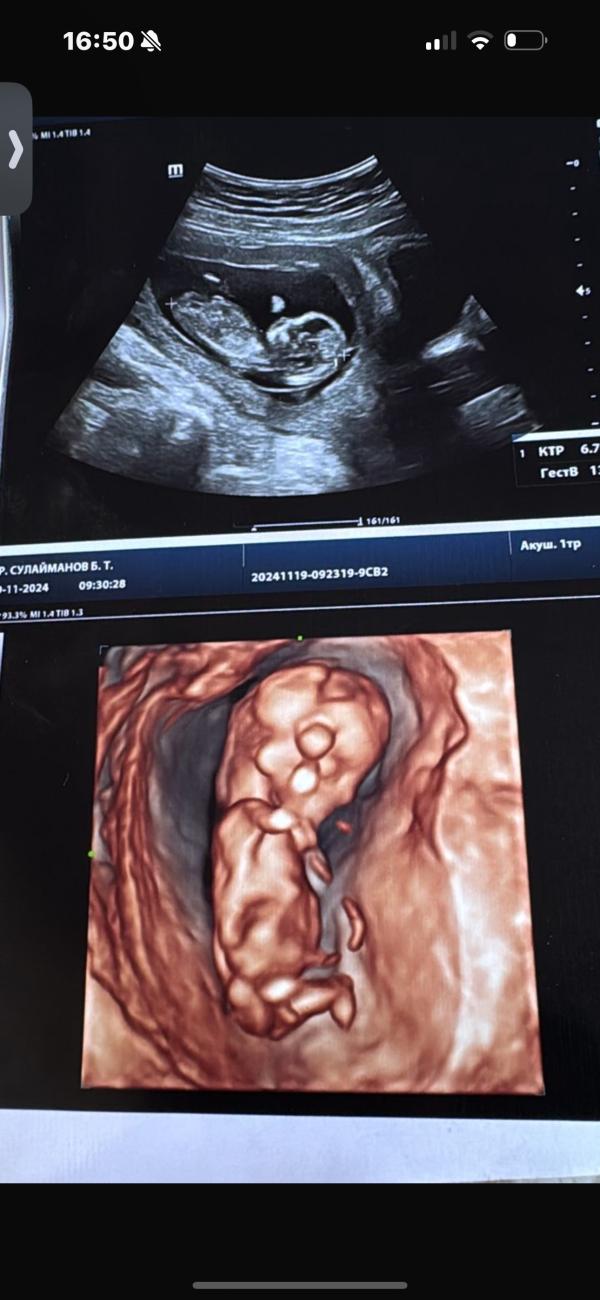

Мальчик или девочка? Не уверен, врач сказал что похоже на мальчика, но есть сомнения...

Сказал что похож на мальчика, но не точно , так как это может быть и половые губы 🙈

13 недель